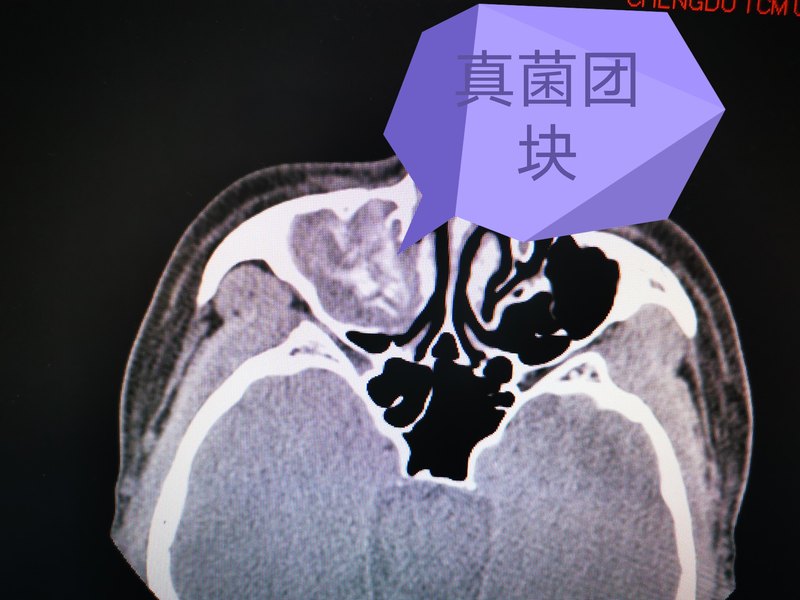

最近來(lái)自廣東佛山順德的劉先生找到耳鼻喉鄭立崗醫(yī)生,77歲的劉先生最近一周鼻涕中帶血,鼻腔有明顯的臭味,不知道是什么情況,在當(dāng)?shù)卦\所找醫(yī)生開(kāi)了點(diǎn)藥物,但是吃了沒(méi)多大效果。所以這次特意過(guò)來(lái)詳細(xì)檢查一下。我初步檢查后考慮可能有真菌性鼻竇炎,給做了鼻內(nèi)鏡檢查,檢查發(fā)現(xiàn)鼻腔中確實(shí)有真菌團(tuán)塊,這種情況必須手術(shù)治療了,吃藥是沒(méi)多大效果的。辦理入院后,給安排了鼻內(nèi)鏡微創(chuàng)手術(shù),插管全麻后內(nèi)鏡下開(kāi)放鼻竇,清除真菌團(tuán)塊。整個(gè)的手術(shù)用時(shí)約50分鐘,非常的順利術(shù)后查房患者無(wú)明顯的不適,無(wú)手術(shù)相關(guān)的并發(fā)癥。術(shù)后在門(mén)診復(fù)查了兩次,術(shù)前恢復(fù)良好,鼻子完全恢復(fù)。對(duì)于鼻子有臭味的患者,及時(shí)的排查真菌性鼻竇炎是非常有必要的。關(guān)于真菌性鼻竇炎如果您還有什么問(wèn)題,歡迎留言和耳鼻喉鄭立崗醫(yī)生進(jìn)一步交流。

真菌性鼻竇炎又稱(chēng)為霉菌性鼻竇炎,是鼻科臨床上一種特殊類(lèi)型的鼻竇炎。根據(jù)是否有侵襲性又分為侵襲性真菌性鼻竇炎和非侵襲性真菌性鼻竇炎。 侵襲性真菌性鼻竇炎多半發(fā)生在免疫缺陷的患者,按病程緩急和臨床特征又分為急性侵襲性和慢性侵襲性,此類(lèi)型病理特征是真菌感染從鼻腔鼻竇內(nèi)侵犯周?chē)]壁黏膜和骨質(zhì),累及眼眶、顱底等周?chē)Y(jié)構(gòu),治療以手術(shù)清除病變,積極抗真菌治療為原則,由于這種類(lèi)型的患者多半免疫力很差,短時(shí)間又無(wú)法提升,所以預(yù)后較差。 而非侵襲性真菌性鼻竇炎根據(jù)類(lèi)型有分為真菌球和變應(yīng)性真菌性鼻竇炎兩種。真菌球型多半發(fā)生在中老年女性,單側(cè)鼻竇發(fā)病,尤其是上頜竇最為多見(jiàn),臨床表現(xiàn)為單側(cè)頭疼、牙疼、面頰疼痛、流涕、涕中帶血、鼻堵、嗅覺(jué)減退、鼻腔異味,也有患者沒(méi)有任何臨床癥狀,是在進(jìn)行頭顱CT、核磁檢查時(shí)無(wú)意中發(fā)現(xiàn)的,但一旦急性發(fā)作會(huì)出現(xiàn)劇烈頭疼,患者會(huì)到急診就診,口服止痛片緩解癥狀,所以發(fā)現(xiàn)問(wèn)題要及時(shí)治療。治療上以手術(shù)治療為主,手術(shù)在內(nèi)鏡下進(jìn)行,術(shù)中打開(kāi)鼻竇,清除竇腔內(nèi)的真菌團(tuán)塊(見(jiàn)下圖),手術(shù)效果較好,復(fù)發(fā)比例很低。 而變應(yīng)性真菌性鼻竇炎則好發(fā)于中青年,可單側(cè)雙側(cè)均可發(fā)病,患者多為過(guò)敏體質(zhì),可合并哮喘,真菌的過(guò)敏原檢查常呈陽(yáng)性,治療以手術(shù)治療加上術(shù)后長(zhǎng)期的激素等藥物治療為原則,此病極易復(fù)發(fā),手術(shù)后一定要叮囑患者長(zhǎng)期、定期隨診用藥。 無(wú)論是真菌球還是變應(yīng)性真菌性鼻竇炎都不推薦全身使用抗真菌藥物。 標(biāo)本瓶?jī)?nèi)是術(shù)中取出的真菌團(tuán)塊,像豆腐渣一樣,這是典型的真菌球型鼻竇炎的表現(xiàn),手術(shù)效果很好。